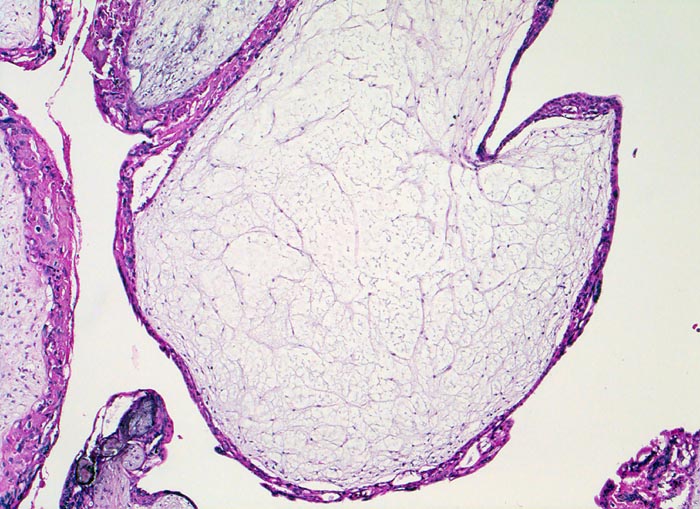

Makroskopisch ist die Plazenta deutlich grösser als erwartet für das Schwangerschaftsalter. Sie ist diffus von bis 2cm grossen Zottenblasen durchsetzt, welche nach Kollaps jedoch der makroskopischen Entdeckung entgehen können. Beim Aufschwemmen in Flüssigkeit entfalten sich die Blasen wieder. Mikroskopisch sind die Zotten aufgrund einer grobblasigen pseudozystischen Hohlraumbildung im Zottenstroma überwiegend grosskalibrig. Im Zottenstroma sind nur ganz vereinzelt Kapillaren nachweisbar. Im Gegensatz zu hydropisch geschwollenen Zotten im Sinne eines Regressionsphänomens zeigen die Zotten bei Blasenmole zusätzlich eine zirkumferentielle Hyperplasie von Synzytio- und Zytotrophoblast mit fakultativer Zellatypie. Bei herdförmiger Mole (> 3725) sind diese Veränderungen nur in einem Teil der Plazentarzotten ausgeprägt.

• Stark vergrösserte und verplumpte Plazentarzotten.

• Hydropisch umgewandeltes Zottenstroma ohne Gefässe mit Ausbildung von pseudozystischen Hohlräumen (Blasen)

• Trophoblastinklusionen und Kerntrümmer im Zottenstroma.

• Überschiessend proliferiertes Trophoblastepithel, teils in der gesamten Zirkumferenz der Zotten mit deutlichen Kernatypien. Kein Embryo.